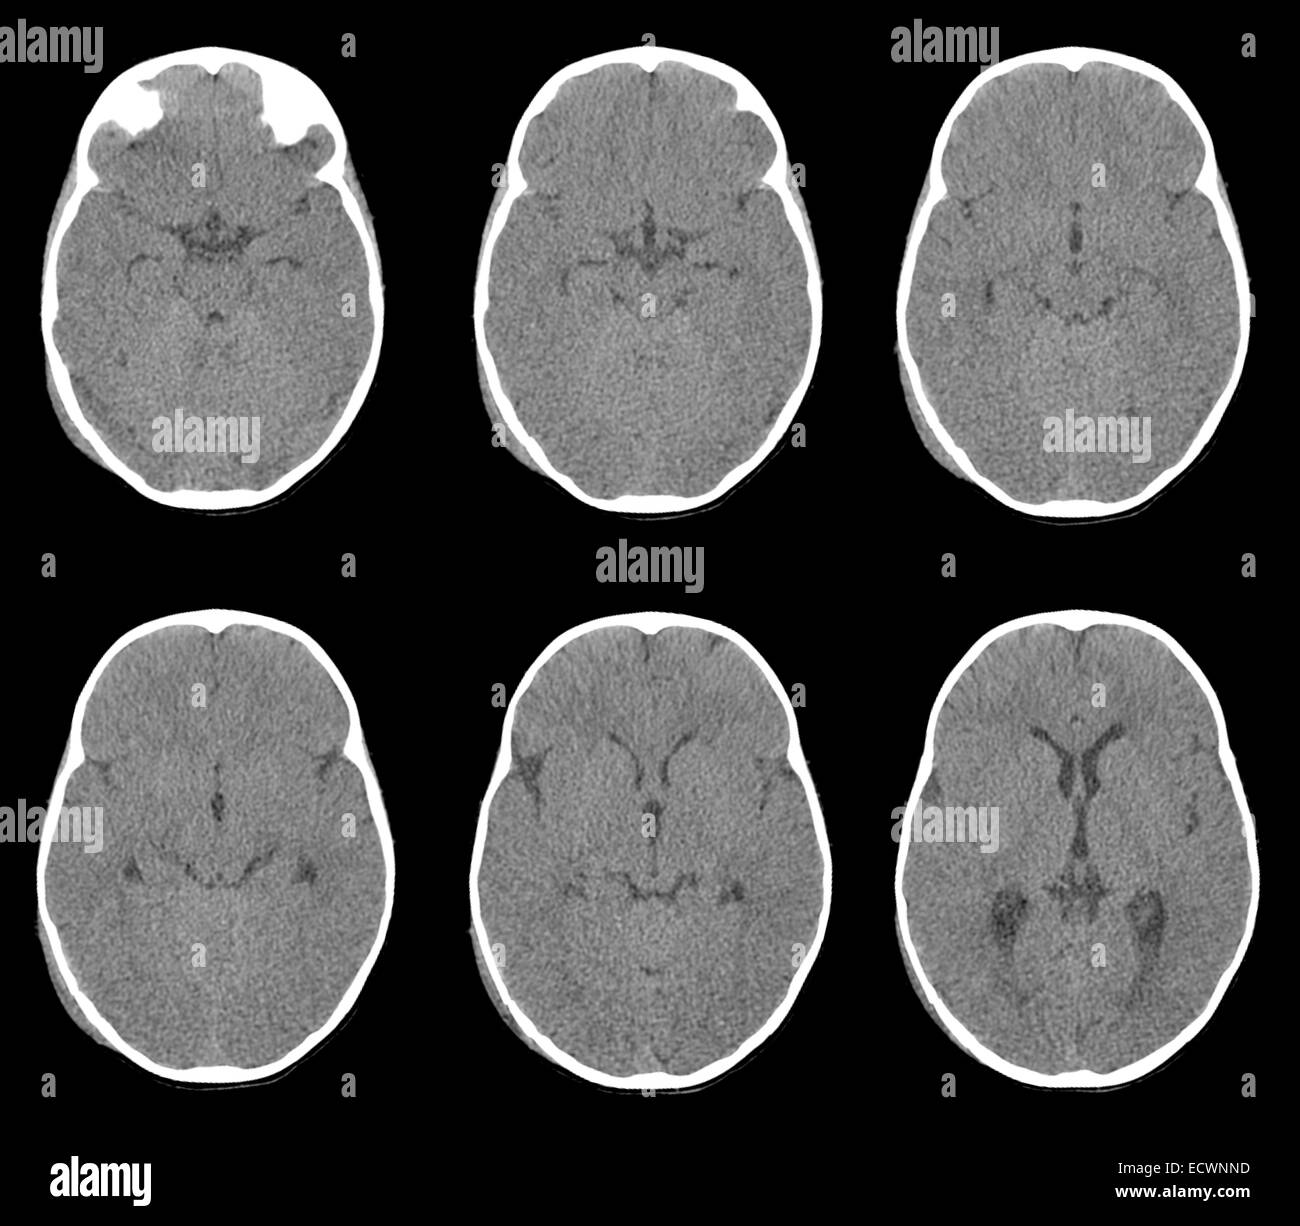

ADAM, Inc está acreditada por la URAC, también conocido como American Accreditation HealthCare Commission (wwwuracorg) La acreditación de la URAC es un comité auditor independiente para verificar que ADAM cumple los rigurosos estándares de calidad e integridad ADAM es una de las primeras empresas en alcanzar esta tan importante distinción en servicios de salud en la red. While bleeding during pregnancy may be a sign of miscarriage, another possibility is a subchorionic hematoma, which is often more manageable. Subdural hemorrhage (SDH) (also commonly called a subdural hematoma) is a collection of blood accumulating in the subdural space, the potential space between the dura and arachnoid mater of the meninges around the brainSDH can happen in any age group, is mainly due to head trauma and CT scans are usually sufficient to make the diagnosis.

Essendo l’ematoma subdurale un’emergenza sanitaria di una certa importanza, per la diagnosi effettiva la risonanza magnetica non è indicata di routine poiché presenta dei tempi di esecuzione nettamente maggiori rispetto alla tomografia computerizzata e non è accessibile a tutti i pazienti (quali ad esempio persone portatrici di pacemaker). Walter Krauland, Walter Krauland, Verletzungen der kortikalen Schlagadern, subdurale Blutung, Verletzungen der intrakraniellen Schlagadern, /, (), (19) Crossref A Norman Guthkelch, The Aetiology and Evolution of Chronic Subdural Haematoma, Topical Reviews in Neurosurgery, /B. Chronic subdural hematoma A chronic subdural hematoma (SDH) is a collection of blood on the brain’s surface, under the outer covering of the brain () It usually begins forming several days or.